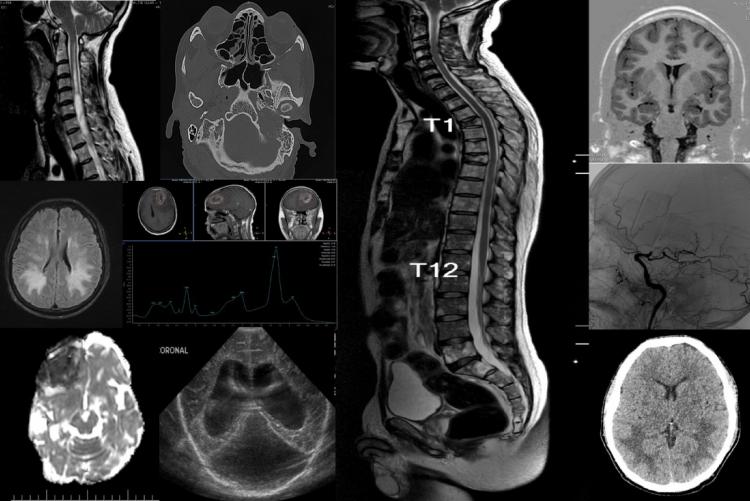

La neuroradiologie est une sous-spécialité de la radiologie, spécialisée dans l'imagerie diagnostique du cerveau, de la colonne vertébrale, de la tête et du cou.

Les neuroradiologues ont une formation en radiologie diagnostique pour étudier diverses maladies telles que les accidents vasculaires cérébraux, les maladies démyélinisantes, les maladies neurodégénératives, les tumeurs cérébrales, les cancers de la tête et du cou, les maladies neurovasculaires, les traumatismes, les douleurs dorsales et d'autres maladies neurologiques.

Les principales modalités d'imagerie sont la tomodensitométrie (Scanner) et l'imagerie par résonance magnétique (IRM).